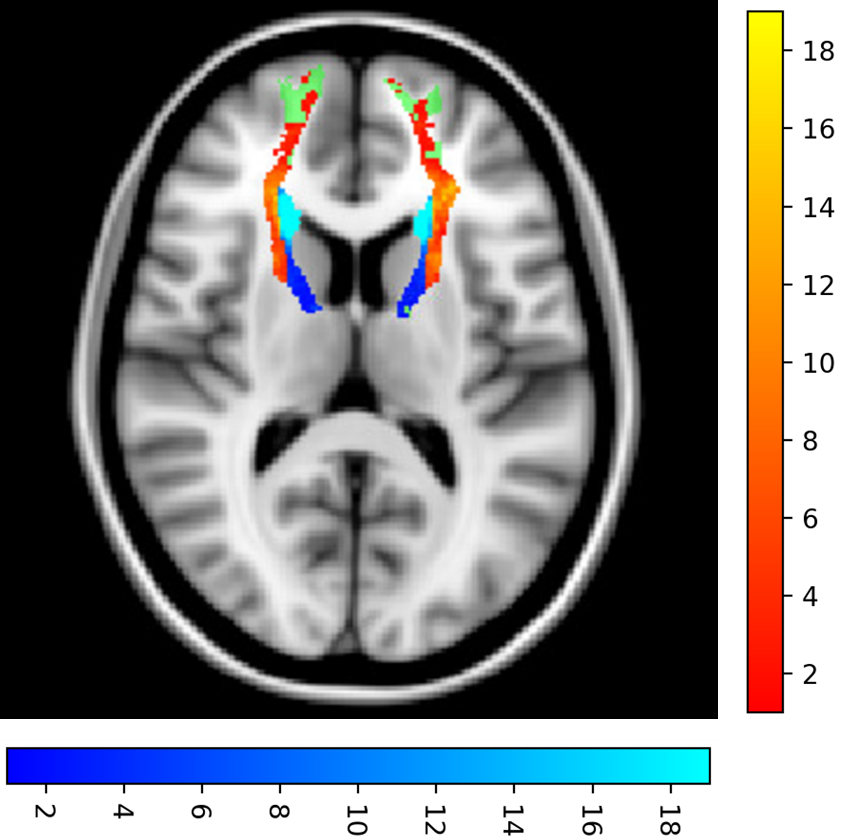

To demonstrate this, we investigated the anterior thalamic radiation (ATR) tract, which has been shown as a key WM tract for processing speed. Increased WMH volume on the ATR has been shown to be correlated with a reduced processing speed [15]. The ATR performed above the global average result for both methods. From figure 2, 68.3% of the ATR WMH voxels are classified as deep WMH. Given periventricular WMH are in the minority, WMH segmentation performance is likely influenced by other unique tract location-based features and not just the distance from the ventricles. This insight could not be captured by the standard global or periventricular and deep white matter evaluation methods.

Figure 2: Ground truth anterior thalamic radiation (ATR) WMH load heatmap across all 60 subjects, with brighter regions indicating higher WMH counts for that given voxel. Blue voxels indicate periventricular WMH voxels and red voxels indicate deep WMH voxels. The units for the colour bars are WMH voxel count for this given slice. The green region indicates the ATR tract, with the WMH voxels overlayed above. The T1w image is the XTRACT T1w template [11].